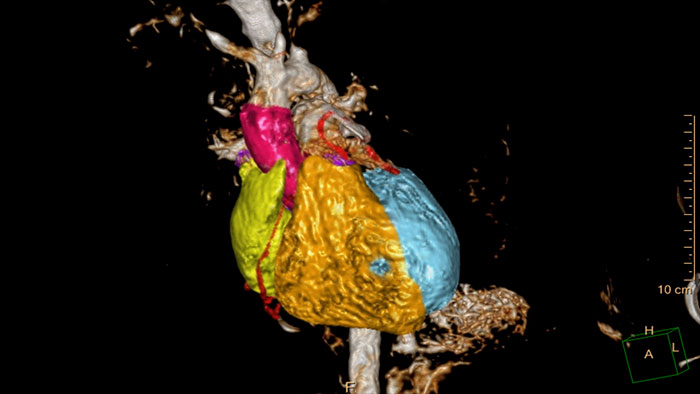

Streamlined modeling workflow

Allows to view volumetric images of anatomical structures, perform segmentation, edit and combine segmented elements (tissues) into a 3D model.

Detailed 3D visualization of the segmented heart

Allows 3D visualization of the heart and vessels anatomy on T1 3D or MRA acquisition. Manual editing tools as well as semi-automatic tools based on seed- and mask-based segmentation can be used as well as full automatic model-based heart segmentation.